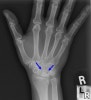

손목관절의 X-ray(PA, lateral) 검사를 시행합니다.

초기에는 월상골이 주위 손목뼈에 비해서 희어 음영이 증가되어 보이고, 진행되명 뼈의 괴사로 인하여 조각이 나고 붕괴가 되며, 결국에는 손목관절의 관절염 소견이 나타납니다.

무혈성 괴사 초기에는 방사선 골 주사나 MRI가 도움이 될 수 있습니다.

X-ray : 키엔벡 병(월상골의 무혈성괴사, Kienbock's disease)